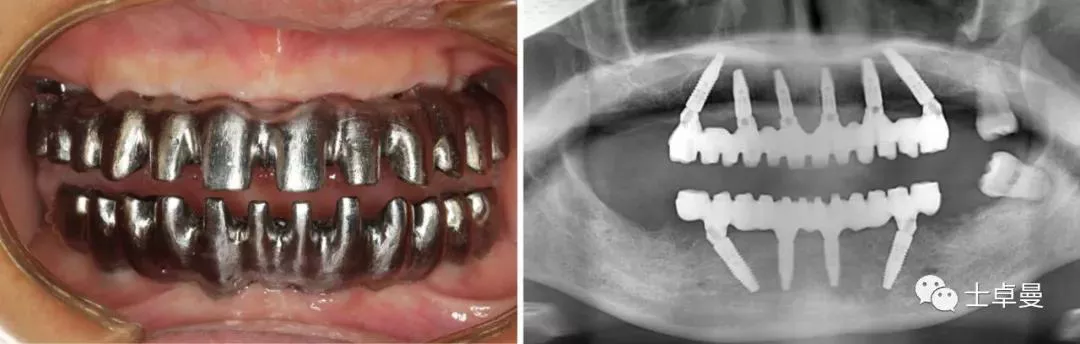

· 手术完成后复查CBCT与术前设计对比,验证植入精度。

· 术后2月,种植体完成骨结合,复查CBCT显示种植体周围骨稳定,未见明显边缘骨吸收;

· 取下临时修复体后口内检查,基台周围软组织健康;